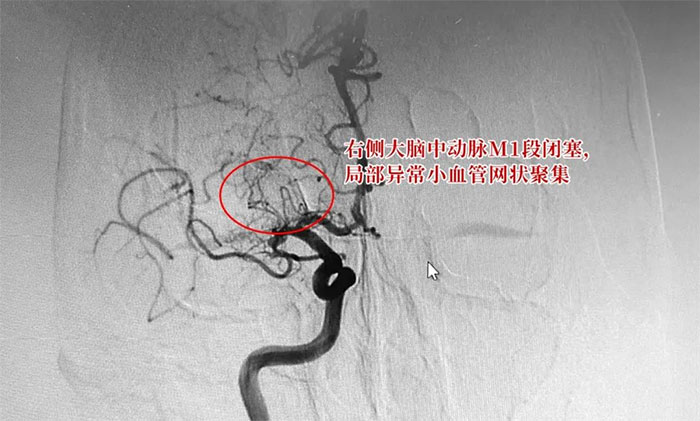

于耀宇主任为患者完善相关检查,通过DSA数字减影血管造影,患者双侧大脑中动脉部分区段存在不同程度狭窄,尤其是右侧大脑中动脉M1段闭塞,局部异常小血管网状聚集。

▲ DSA检查示:右侧大脑中动脉M1段闭塞,局部异常小血管网状聚集